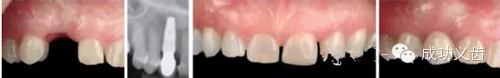

图3.即刻种植1,2008年的拔牙即刻种植病例,完美修复效果。

图4.即刻种植2,2013年复查。种植体周围骨组织稳定,龈乳头依然尖锐。颜色粉嫩,赏心悦目。